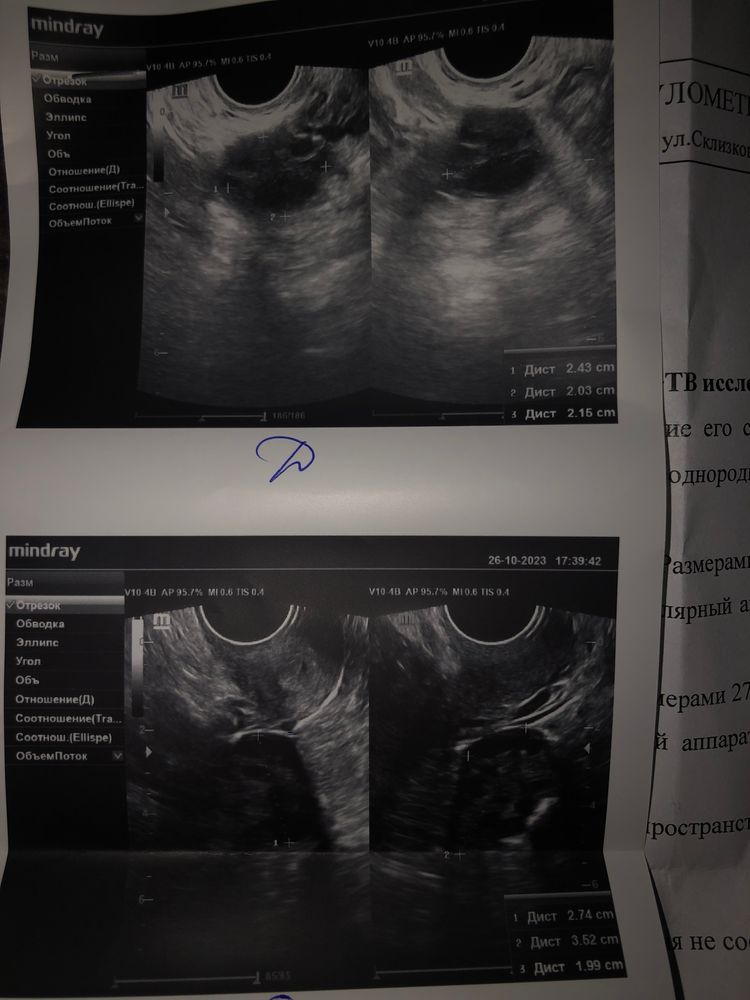

Девочки , сегодня была на узи , так как сильная колющая боль в правом яичнике ,обычно такая боль у меня к овуляции ,вот интересно было овуляция ли, есть ли доминантный фолликул. Узист сказал что в левом яичнике фолликулы 4-5мм, правый долго рассматривала ,когда спросила есть ли ДФ, сказала непонятно ,но в конце сказала что максимум фолликул -8 мм в правом яичнике

фото узи , кто разбирается, есть ли тут доминантный фолликул? Ужасно болит правый яичник как при доминантном фолликуле или при овуляции

Фоликулы хорошие,но доминантного нет. У вас или дц 7-8 или овуляции не будет

Людмила Стаценко, получается 8мм это не доминантный фолликул?

bravo gun, он сильно маленький для того чтобы выйти, какой у вас дц? В заключение узи нашли причину боли?

bravo gun, фолликулу нужно размер и массу набрать примерно когда он вырастет с 8мм до хотя бы 18-22мм он сможет выйти, если не успеет то он просто угаснет и овуляции не случиться, пока он 8 мм ждём)))